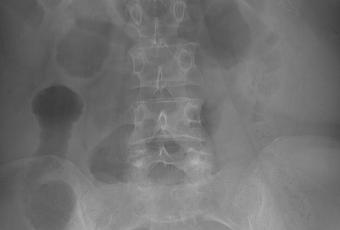

Paciente femenino de 59 años de edad, casada. Ama de casa. Toxicomanias negadas. Alergias negadas. Histerectomia hace 20 años por miomatosis uterina. Antecedente madre finada por cáncer de colon. Refiere que desde finales De mayo del 2017 a perdido más de 7 kilos en 3 meses, pesando 71.100 kilos y ahora 63.900kg (10%), además de dolor epigastrico, punzante, ademas de poca intolerancia a la via oral, vomito en numero de 2 de contenido alimenticio, no biliar. A la exploración signos vitales TA 100/70 mm Hg FC: 80x FR: 20x SatO2: 98% T:36.1 paciente conciente, orientada, palidez (++), normocefalo, buena implantacion del cabello, pupilas isocoricas, mucosa moderadamente hidratadas, cuello sin adenomegalias, cardiorrespiratorio ruidos cardiacos normales, murmullo vesicular normal, abdomen blando depresible, doloroso en epigastrio e hipocondrio izquierdo, no se palpan viceromegalias, giordano izquierdo (+). No se palpan ganglios inguinales. Exploracion rectal no se obsvervan hemorroides o fistulas rectales. Extremidades integras, no edema. Se toma Placa simple de abdomen de pie.

El volvulo sigmoide es una causa de obstrucción del intestino grueso y ocurre cuando el colon sigmoide se tuerce en el mesocolon sigmoide.